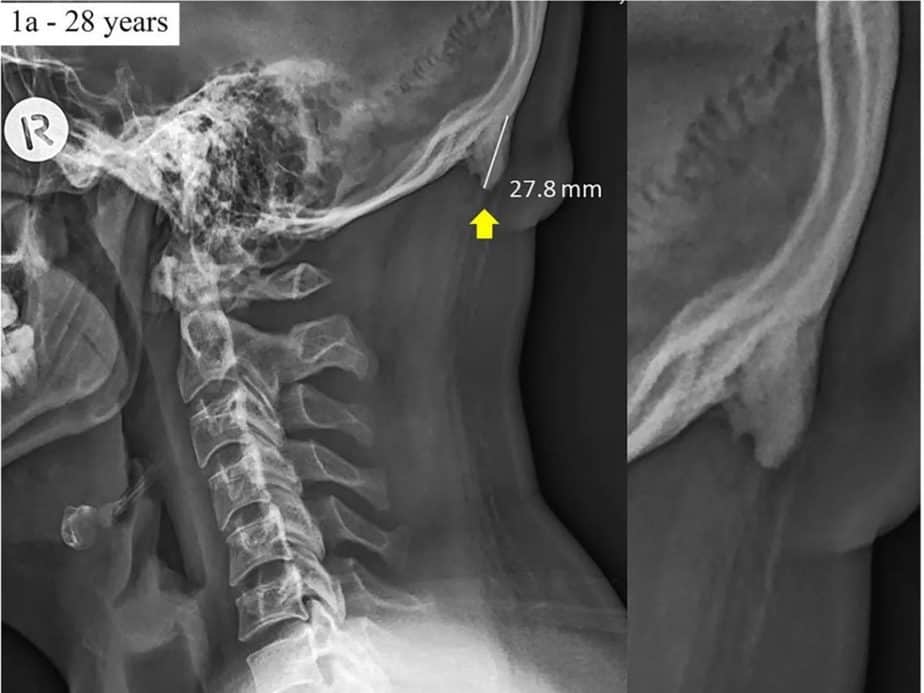

Dilansir dari Ubergizmo, tanduk tersebut tumbuh di pangkal tengkorak kaum muda. Kondisi itu dikenal dengan istilah pembesaran oksipital eksternal.

Dikutip Telset.id, Jumat (21/06/2019), pembesaran oksipital eksternal lebih menyerang mereka yang berusia 18 tahun sampai 30 tahun. Dijelaskan para peneliti, tanduk itu merupakan respons evolusioner terhadap kehidupan modern manusia.

Para peneliti menyebut, pembesaran oksipital eksternal terjadi karena saat ini manusia, umumnya generasi milenial, menghabiskan banyak waktu untuk menatap ponsel. Akibatnya, terjadi ketegangan di leher.

“Pertumbuhan tanduk-tanduk tersebut adalah cara kerangka untuk menghadapi ketegangan. Kami berhipotesis, hal itu terjadi lantaran postur menyimpang berkelanjutan terkait penggunaan ponsel dan tablet,” terangnya.

Mereka melanjutkan, tanduk tersebut tidak berbahaya. Keberadaannya hanya mengindikasikan bahwa kepala dan leher dan tidak dalam konfigurasi yang tepat dan mengimplikasikan ada sesuatu hal buruk di bagian lain.